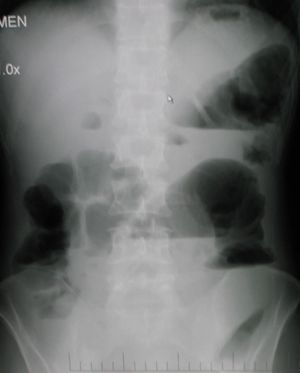

تتمثل أهم طرق التشخيص التي يمكن إجراؤها في حالة انسداد الأمعاء في اختبارات الدم أو عمل أشعة إكس على البطن أو الأشعة المقطعية و/أو أشعة الموجات فوق الصوتية. وإذا ما تم اكتشاف وجود ورم أو تكتل في الأمعاء، فقد يتم استئصال نسيج منه لتحليله وفحصه لمعرفة طبيعة هذا الورم أو التكتل.

من ضمن الأشياء التي يكشف عنها التصوير الإشعاعي وجود انتفاخ بالأمعاء ووجود مستويات متعددة (أكثر من ستة مستويات) من السوائل والغازات في صور الأشعة التي تؤخذ على البطن والمريض في وضع الاستلقاء على الظهر تارة والوقوف تارة أخرى.

وعلاوةً على ذلك، فمن الممكن استخدام حقنة الباريوم الشرجية أو صور أشعة ملونة للأمعاء الدقيقة أو الأشعة المقطعية لتحديد درجة انسداد الأمعاء، وما إذا كان الانسداد جزئيًا أم كليًا، وكذلك لمعرفة سبب الانسداد.